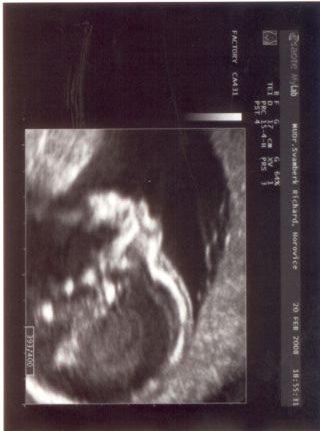

23+3tt